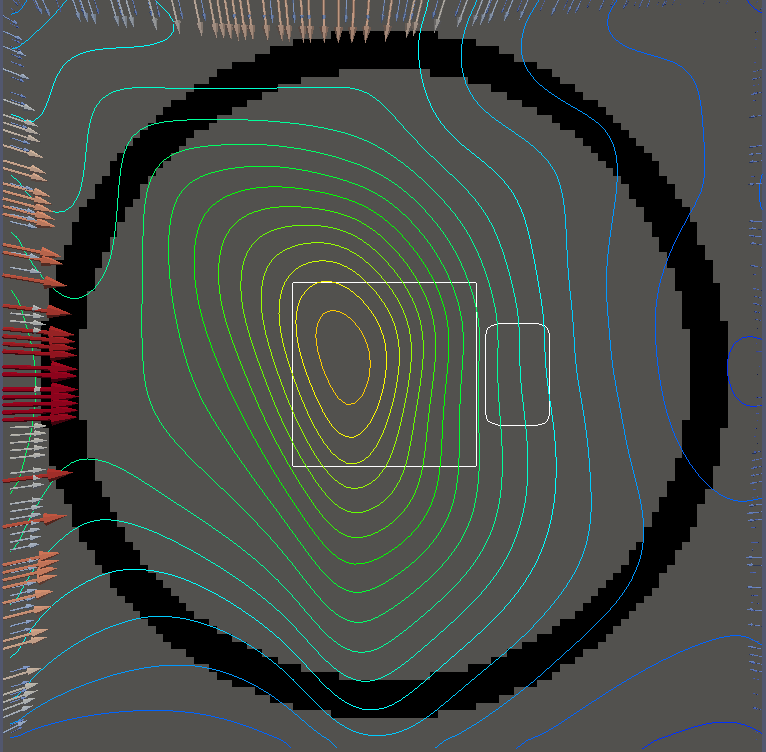

For testing, we use three tumor/risk region regions similar to those in [13]. Specifically, we define the regions in Table 3 and are shown in Figure 1; the void region is shown in black and the tumor and risk regions are traced in white. In the basic target case, seen in Figure 1(a), the tumor region is a box, as is the risk region. The second, intermediate target case, seen in Figure 1(b), involves an L-shaped tumor around a box-shaped risk region. Finally, the complex target case in Figure 1(c) involves a C-shaped tumor around a risk region.

We will solve both and for each geometry seen in Figure 1. For for each example, we set on and elsewhere, corresponding to an average (over time) dose of and

Figure 2 shows the optimal boundary source term for both and The vectors shown on the boundary are the time-integrated values of normalized and then scaled by In Figures 2(a), 2(c), and 2(e) (corresponding to ), the isolines are spaced at intervals of the maximum of the desired dose (here, 5). In the intermediate and tracking cases, we see that relatively low dose levels are attained, primarily due to the high penalty to any dose deposited in the risk region. In Figures 2(b), 2(d), and 2(f)(corresponding to ), the isolines are spaced at intervals of of cells killed. Here a high proportion of the tumor cells are killed (in each case ) while in the Intermediate and Basic cases, the tumor has at least survival; in the Complex case, the risk region has survival.